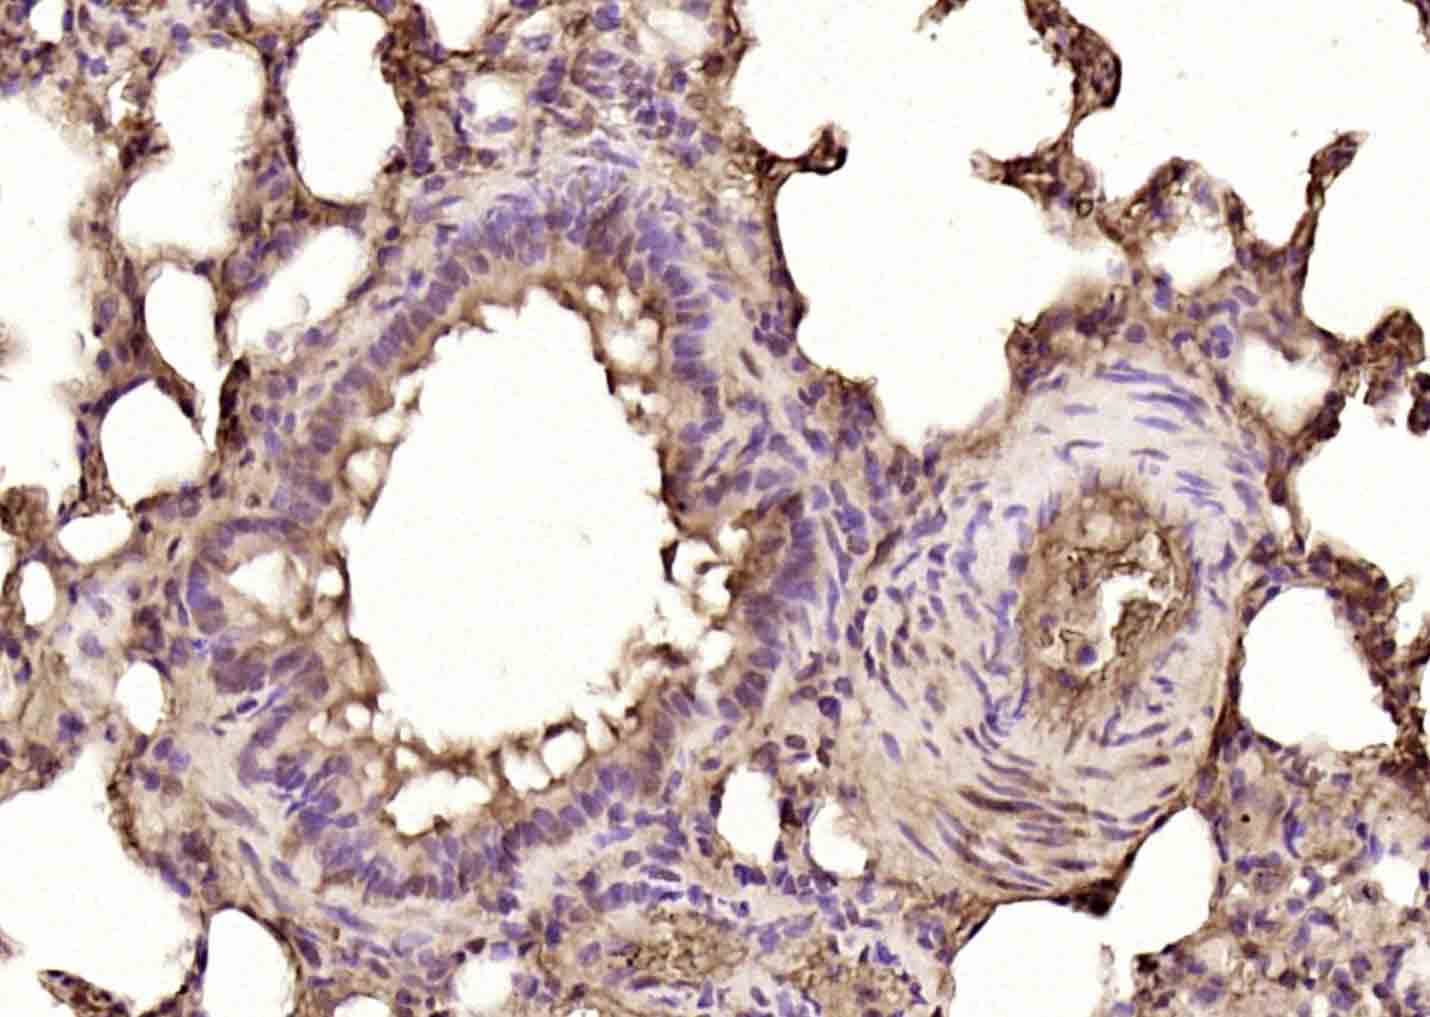

Paraformaldehyde-fixed, paraffin embedded (rat lung); Antigen retrieval by boiling in sodium citrate buffer (pH6.0) for 15min; Block endogenous peroxidase by 3% hydrogen peroxide for 20 minutes; Blocking buffer (normal goat serum) at 37°C for 30min; Antibody incubation with (TMP21) Polyclonal Antibody, Unconjugated (bs-21954R) at 1:200 overnight at 4°C, followed by operating according to SP Kit(Rabbit) (sp-0023) instructionsand DAB staining.